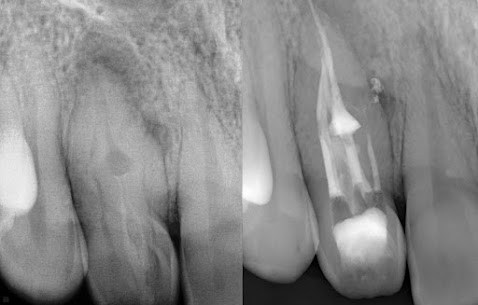

Przypadek 1.

Pacjentka zgłosiła się celem kontynuacji leczenia kanałowego, rozpoczętego w innym gabinecie.

W badaniu wewnątrzustnym stwierdzono nietypową budowe korony zęba, a dzięki pogłębionej diagnostyce rentgenowskiej potwierdzono rozpoznanie. W powiększeniu mikroskopu zbiegowego oraz przy użyciu najnowocześniejszych narzędzi rotacyjnych uwidoczniono i opracowano wszystkie kanały, które następnie zostały wypełnione termicznie uplastycznioną gutaperką.

Kontrola rentgenowska potwierdziła prawidłowy przebieg leczenia kanałowego.